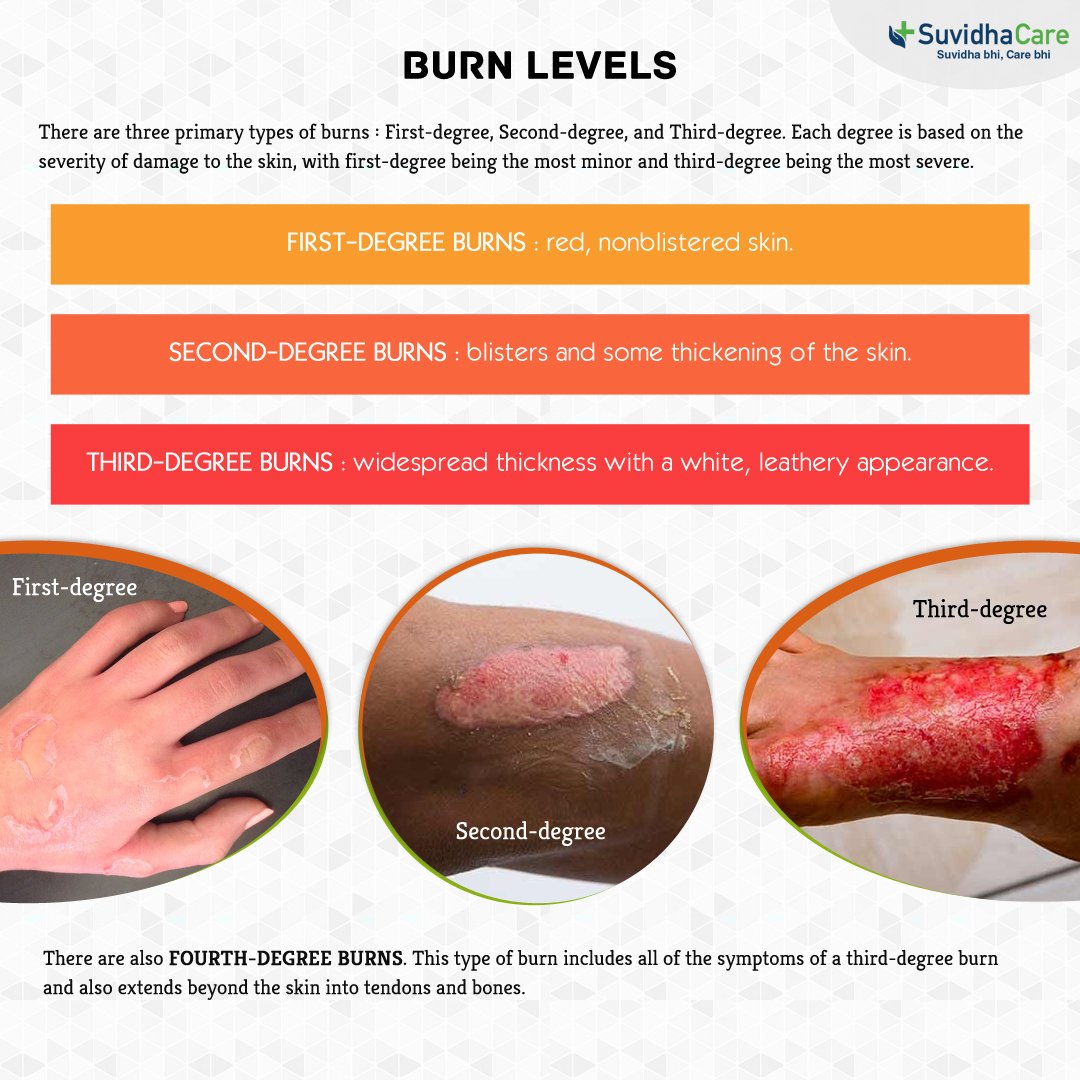

Burns First Aid Guide

Leathery Skin After Burn

Medical Vector Illustration Burn Stages Degree Burns Of Skin 8910124

Leathery Skin After Burn

3 Astme P letus Mis See On Ravi Ja Paranemine SFOMC